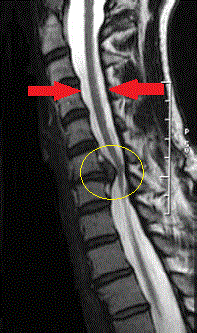

Boyun fıtığında en güvenilir teşhis, hekimin yapacağı muayenedir. Burada, hastanın şikayetleri ve hekimin muayene bulguları en önemli tanı kriterleridir. Kesin tanıya götüren tetkikler ise; MR (en sık kullanılan), bilgisayarlı tomografi, röntgen ve EMG (elektromyografi)'dir (Resim 4).

Resim 4: Omuriliği (yukarıdan aşağı uzanan, iki kırmızı ok arasında gösterilen beyaz alan) sıkıştırmış bir boyun fıtığının (sarı daire içerisinde) MR görüntüsü.